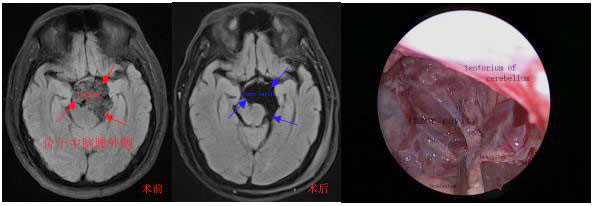

病例3:神经内镜结合显微镜经颅切除桥小脑角区-斜坡区-鞍区复杂表皮样囊肿